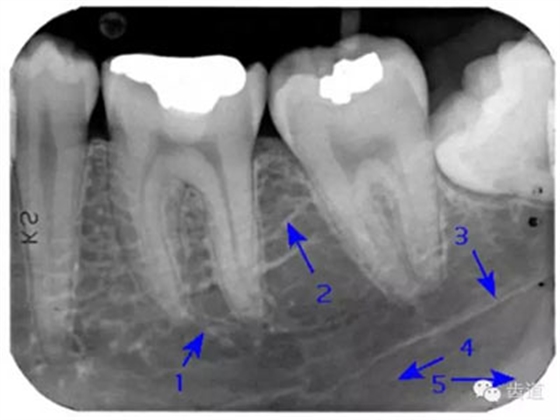

是機(jī)體中鈣化最高和最堅(jiān)硬的組織,X線片上的影像密度也最高,似帽狀被覆在牙冠部牙本質(zhì)的表面。后牙頜面、前牙切緣最厚,由頜面和切緣向側(cè)方至牙頸部逐漸變薄,終止于牙頸部。

牙頸部Burnout征象:有時(shí)因投照技術(shù)問(wèn)題而造成牙頸部近中或遠(yuǎn)中呈低密度影像,位于牙釉質(zhì)和牙槽嵴頂之間。

圍繞牙髓構(gòu)成牙的主體,牙本質(zhì)中礦物質(zhì)的含量比釉質(zhì)少,X線影像的密度較牙釉質(zhì)稍低。

被覆在牙根表面,為一層很薄的組織,密度與牙本質(zhì)相當(dāng) 。

髓腔可分為冠部的髓室和根部的根管。牙髓內(nèi)含牙髓軟組織,X線片上顯示為密度低的影像。年輕人的牙、牙根未完全形成時(shí),根尖孔粗大,牙髓腔大。隨著年齡的增長(zhǎng),牙本質(zhì)逐漸增多,髓腔愈狹窄,根尖逐漸變細(xì)。

是上下頜骨包圍牙根的突起部分,又稱牙槽突或牙槽嵴。X線片上牙槽骨所顯示的密度較牙低。上牙槽骨的密質(zhì)骨薄,松質(zhì)骨多,即骨小梁數(shù)目多,相交處呈密度高的點(diǎn)狀影像,骨髓腔則呈點(diǎn)狀密度低的影像,固上牙牙槽骨的骨小梁結(jié)構(gòu)X線片上呈顆粒狀影像;

牙槽骨:下牙槽骨密質(zhì)骨厚而松質(zhì)骨少,骨小梁多呈水平方向排列,骨髓腔呈三角形和大小不等的圓形密度低的影像,所以下牙槽骨的骨小梁結(jié)構(gòu)呈網(wǎng)狀結(jié)構(gòu)

即固有牙槽骨,是牙槽骨的內(nèi)壁,圍繞牙根,骨質(zhì)致密而薄,X線片上顯示為包繞牙根的連續(xù)不斷的密度高的線條狀影像。

是介于牙槽窩和牙骨質(zhì)之間的結(jié)締組織。牙周膜的厚度一般在0.15~0.38mm之間。X線上顯示為包繞牙根連續(xù)不斷的密度低的線條狀影像,其寬度均勻一致